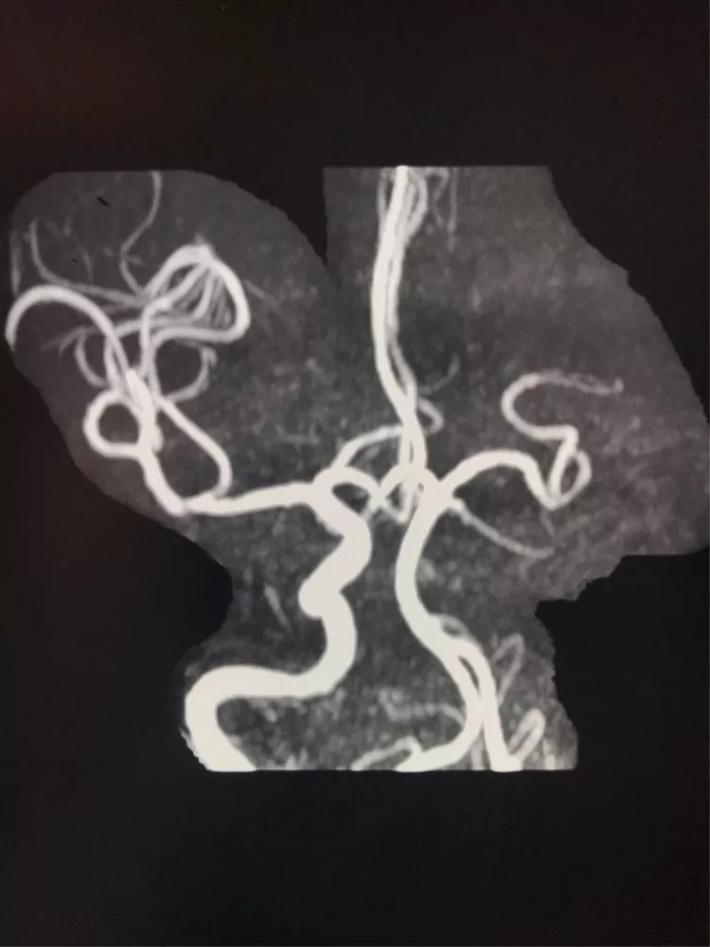

MRA显示:左侧大脑中动脉闭塞。

脑血管造影显示:右侧大脑中动脉闭塞。